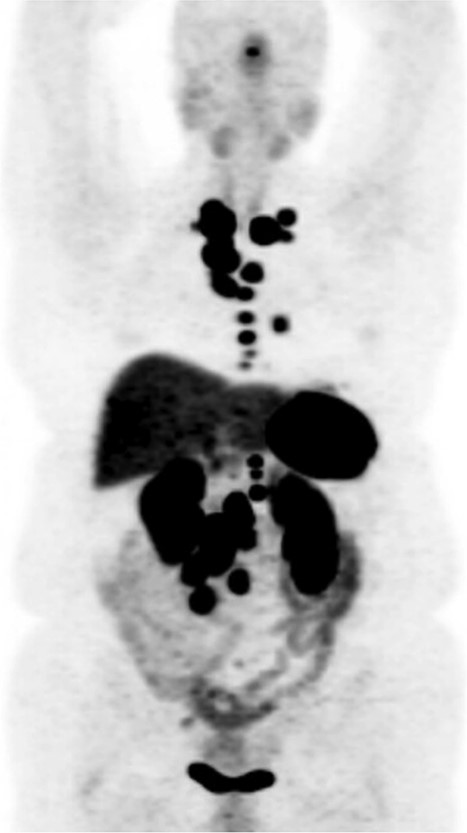

DOTATATE positron emission tomography-computed tomography scan revealing extent of metastatic disease.